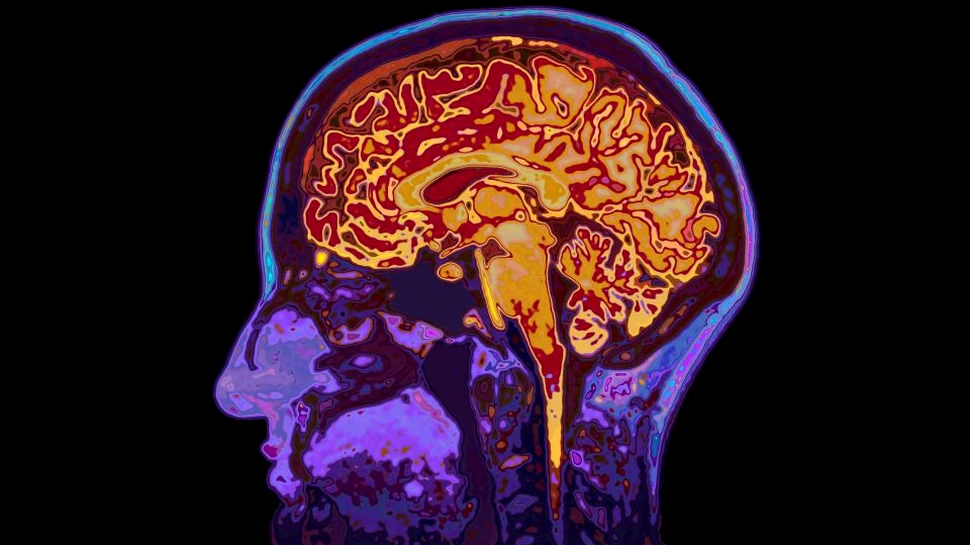

Un nou studiu arată că avem mai puţin control asupra alegerilor personale decât se credea anterior, iar activitatea inconştientă a creierului determină alegerile noastre înainte să fim conştienţi de ele.

Publicat în Scientific Reports, noul experiment a fost realizat în laboratorul Future Minds de la UNSW School of Psychology şi a arătat că alegerile pot fi prezise prin intermediul tiparelor activităţii cerebrale cu 11 secunde înainte ca oamenii să ia o decizie conştientă, scrie Medical Xpress.

Experimentul a avut în vedere alegerea de către participanţi a două tipare vizuale de dungi roşii şi verzi, una orizontală, iar cealaltă verticală (ca în imaginea de mai jos), înainte de a le vizualiza. În acest timp, subiecţii au fost analizaţi cu RMN.

Cercetătorii nu doar au prezis ce tipar vor alege, ci şi cât de puternic participanţii au putut să-şi imagineze. Cu ajutorul tehnologiei de machine learning, cercetătorii au ajuns la concluzia că predicţiile alegerilor participanţilor au avut loc cu 11 secunde înainte de decizia conştientă.

Regiunile creierului care au scos la iveală informaţii despre viitoarele alegeri au fost localizate în zonele executive – unde se iau deciziile conştiente – dar şi în structurile vizuale şi subcorticale, ceea ce sugerează existenţa unei reţele ample responsabile pentru naşterea gândurilor.